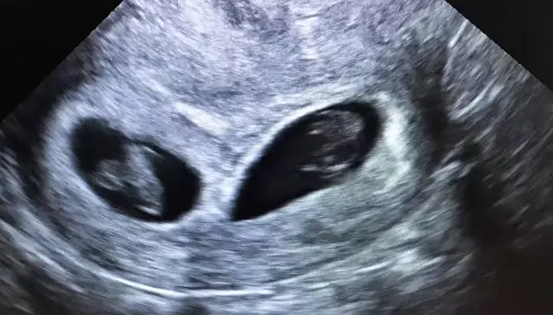

但是需要注意的是,通过hcg的多少来判断女性是否怀的双胎并不是很准确,建议大家还是在怀孕11-13的时候到医院进行B超检查,查看宫腔内胎儿的数量,进一步确定是否是怀孕双胎。